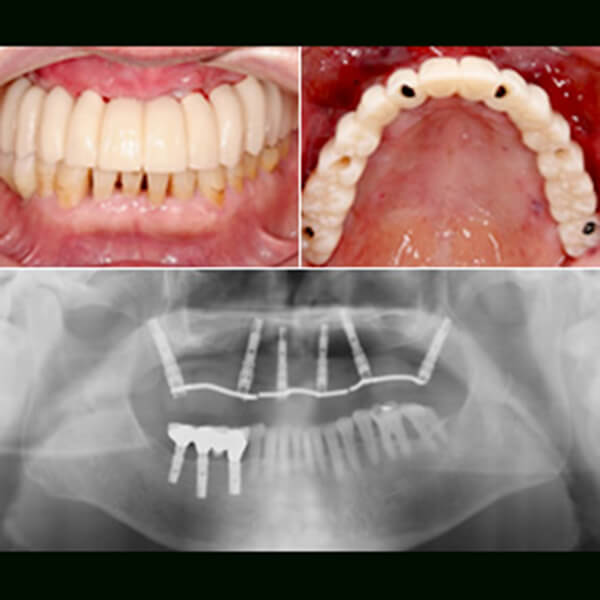

オールオン4

オールオン4とは?

総入れ歯の方や多くの歯をなくされた方への最先端のインプラント治療法です。奥のインプラントを骨のある部分へ斜めに埋入します。

インプラントにかかる力を均等にわけて、骨の中での安定性を確保させ最小4本のインプラントで全ての人口歯12本を支える方法です。

6本のインプラントで全ての歯を支えるのがオールオン6です。

術前

(上の歯が一本も無い状態)

治療計画

レントゲン、CT撮影にて治療計画(ノーベルガイドを用いたシュミレーション)

フラップスで手術

ノーベルガイドを用いて6本のインプラントをフラップスで手術

術後

(その日の内に仮歯を装着)

最終的なブリッジ

約半年後に美しい仕上がりの最終的なブリッジが入ります